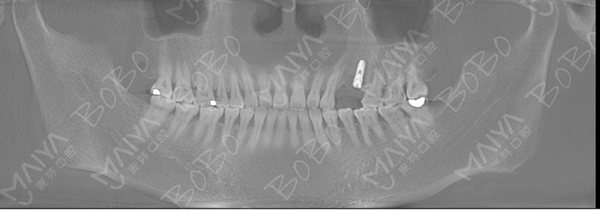

种牙成功后口腔ct全景片

根据赵女士的情况,麦芽口腔院长提醒广大牙缺失患者,不要长期置缺牙不理,不然不仅会出现像赵女士一样牙龈萎缩、牙槽骨吸收、增加种植难度,身体健康也面临着各种隐忧。